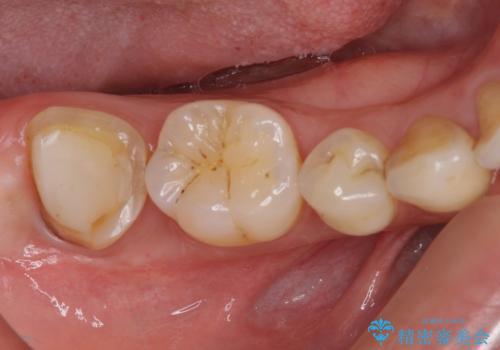

根管治療後の補綴治療 奥歯のセラミッククラウン

- 根管治療の専門医院で根管治療を行った後、セラミッククラウンによる補綴治療を希望して来院された患者様です。

根管治療後の土台も構築されていたので、仮歯に置き換えた後にフルジルコニアクラウンにて補綴することとしました。